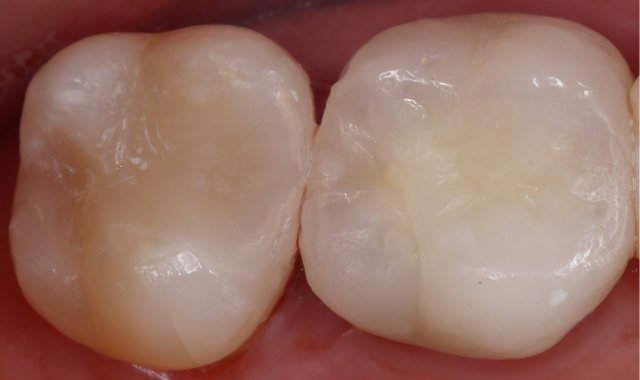

A post-operative picture and radiograph were taken to confirm ideal restoration placement with sealed proximal margins and a void-free restoration (Figs. 14-15).

Fig. 14

Fig. 15

Direct restorations can be challenging to complete with ideal results. The procedure begins with ideal isolation and is completed with regard to proper band placements and utilization of materials that facilitate ideal outcomes. Even larger restorations are completed with efficiency utilizing bulk fill restoratives that can provide not just shorter chair times for patients but also esthetics that exceed patient expectations.